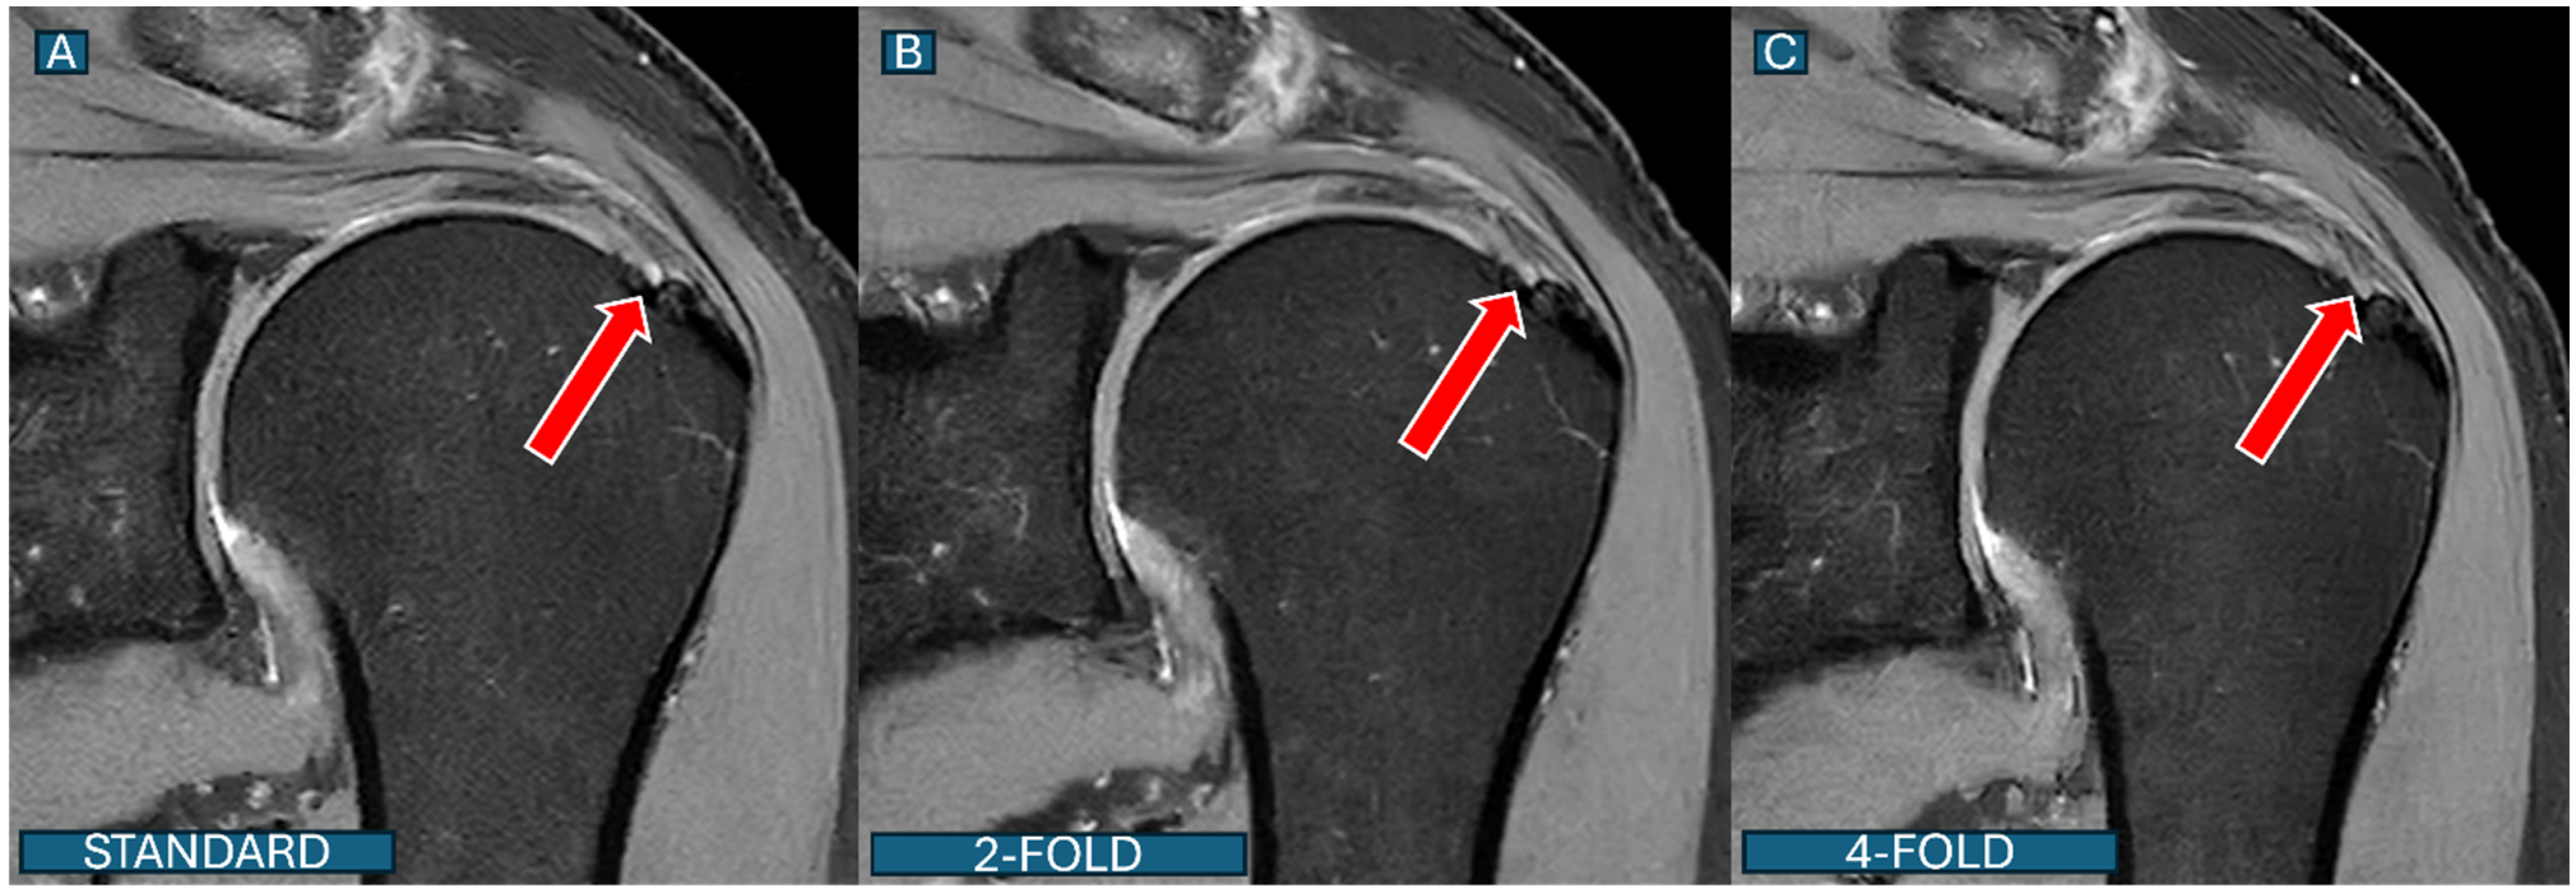

Figure 6. Labral tear detection across protocols. Coronal PD fat-saturated images show a superior labral anterior–posterior (SLAP) lesion (red outline) in a 36-year-old athlete. (A): Standard protocol; (B): DL2 protocol; (C): DL4 protocol. The lesion is well visualized in both the standard and DL2 protocols, while subtle degradation in lesion conspicuity is noted in the DL4 protocol, though the lesion remains clearly detectable.